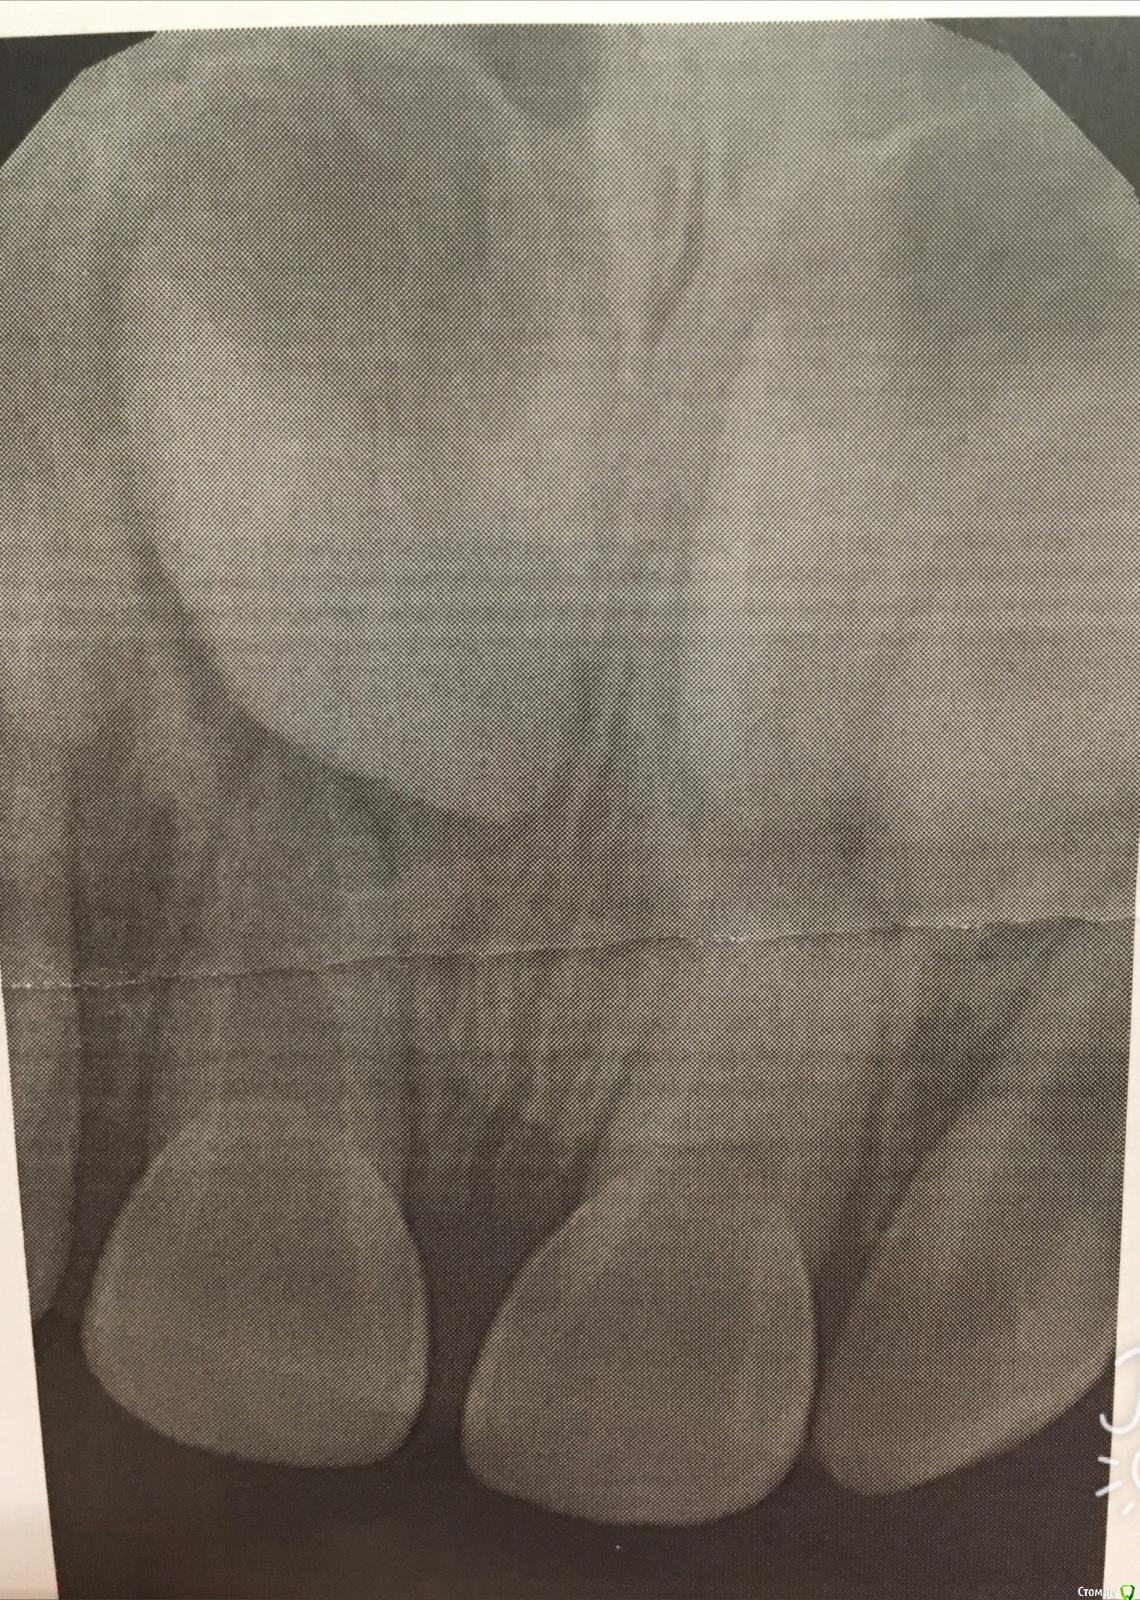

Сильный ушиб передних верхних зубов, периодонтит, 2,8 г.

1,5 месяца назад упали с высоты, разбили рот, неполный вывих двух передних верхних зубов (51, 61)(посередине). Зубы шатались немного при надавливании, кровоточили сильно по краю десневому, остались немного вдавлены назад, может 1-2 мм, не сильно, правый чуть больше левого.

Рентген снимок показал, что переломов нет. Прошло 1,5 месяца, эти зубы немного потемнели (на фоне остальных зубов совсем немного), правый до сих пор шатается, хотя, кажется, что меньше (но может и это квжется мне).

На осмотре врач ставит периодонтит этого правого зуба, показания к депульпированию. Второй (левый) под вопросом, надо вскрывать и смотреть, говорит....

Врач считает, что идет резорбция корня, требуется депульпирование, которое тоже неизвестно сохранит ли зуб.

Прикрепляю первый рентген.